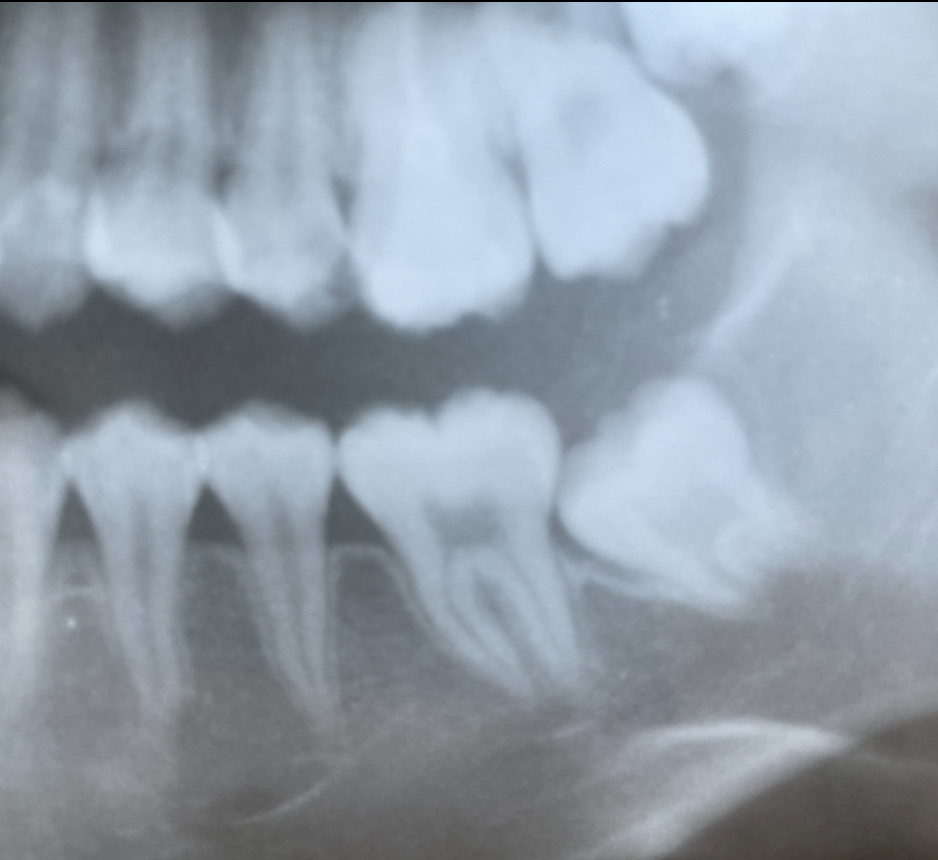

こちらの写真は、10才女の子のレントゲン写真です。

下顎の6歳臼歯に、虫歯ができています。

虫歯の状態は、歯槽骨よりも深く、治療することが不可能な状態です。

この歯の一つ後ろに存在する第二大臼歯は、もうまもなく萌出(ほうしゅつ)すると予想されます。